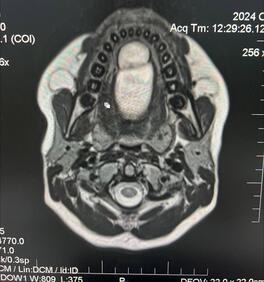

В отделении челюстно-лицевой хирургии нашей больницы успешно выполнена плановая операция по удалению кисты подъязычной области у ребёнка. Хирургическое вмешательство провёл челюстно-лицевой хирург Хажгириев Алик Лечиевич.

Поводом для обращения за медицинской помощью послужили жалобы родителей на появление у ребёнка раздражительности, отказ от приёма пищи и постепенно усиливающийся отёк в переднем отделе шеи. Проведённое клиническое и инструментальное обследование выявило наличие кистозного образования с вовлечением подъязычной кости.

В рамках хирургического лечения была выполнена цистэктомия — полное удаление кисты — с частичной резекцией подъязычной кости. Операция прошла успешно, без интра- и послеоперационных осложнений. В настоящее время состояние пациента оценивается как стабильное, с положительной динамикой восстановления.